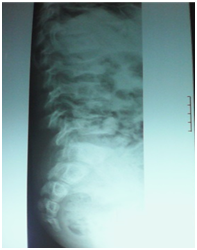

A 12-year-old boy was diagnosed with Sickle Cell Disease (SCD) with genotype SS about one year prior to. He presented with 2 months history of inability to walk and pain in both legs to Komfo Anokye Teaching Hospital in Kumasi, Ghana. The complaints were associated with marked weight loss and generalized body pain. He had been admitted about 2 weeks prior to the onset of current symptoms on account of abdominal pain and anaemia where he was haemo-transfused, given medications and subsequently discharged. There were no other significant findings in the past medical history, immunization history, nutritional and developmental histories. On examination he was found to be wasted (Weight for Height z-score <-3SD), pale, afebrile and anicteric. He had palpable axillary and inguinal lymph nodes (each measuring about 1cm to 1.5cm, mobile, non-tender and not matted). Vital signs were normal on admission. Other significant examination findings were obvious swelling of the right leg which was warm to touch, erythematous and tender on palpation. He had a gibbus deformity of the lower thoracic spine with no remarkable neurological findings in the lower limbs. A diagnosis of SCD with vaso-occlusive crises and cellulitis of the right leg was made with differential diagnosis of osteomyelitis, Deep Vein Thrombosis and Potts disease. Initial investigations revealed WBC of 13.51 X 109/dl with Neutrophils 8.83 (65.3%) Lymphocytes 4.27 (31.6%) and Monocytes 0.25(1.9%), Hemoglobin 7.1g/dl, MCV-70.7, MCH-22.4, Platelets: 538, ESR-117, INR-1.05, Prothrombin Time-14.3secs and blood sugar-6.5mmol/L. Malaria parasites were not seen on the blood smear and patient was negative for Retro-Viral Screen for HIV. Other investigations included Doppler Ultrasound, Chest X-ray, Pelvic x-ray, Thoraco-lumbo-sacral spine X-ray (Figure 1-10). Blood culture and sensitivity could not be done at the time of admission as microbiology service in the hospital had a brief logistic challenge. Radiological findings revealed the following: Reduction in the vertebral body heights of T7-T10 with associated reduction in the intervertebral disc spaces and crowding of the posterior ribs. A paravertebral soft tissue mass extending from T4 vertebral level to T11. Coarse trabeculation and sclerosis of the ribs noted. Expansion of the anterior end of the left 8th rib with ill-defined lytic areas. Buckling of the cortex of the lateral aspect of the left 9th rib, suggestive of a fracture. The imaged portion of the proximal humerus shows periarticular osteopenia. Also noted was relatively small left humeral head with left glenohumeral joint space. There are patchy homogenous opacities in both lung fields predominantly in the lower zones. There was associated silhouetting of the hemi diaphragms bilaterally and the cardiac shadow. There was generalized sclerosis of the imaged pelvic bones with coarsening of the trabeculae. The right femoral head was deformed and expanded with sclerosis and lytic areas within. There was associated narrowing of the right hip joint space. The left femoral head also showed patchy lucencies. No deformity of the left femoral head seen. The left hip joint space appeared normal. Also noted was fusion of the sacroiliac joints bilaterally. There was diffuse sclerosis of the imaged vertebrae with coarse trabeculae. The vertebral endplates of L1/L2 and L3/L4 showed sharp depression at the margins with a flat base centrally giving it the H shaped appearance. Also noted were ill-defined lytic areas in the L3 to L5 vertebrae with associated end plate irregularities and reduced intervertebral disc spaces at L3/L4 and L4/L5. No paravertebral soft tissue mass seen. No fracture or listhesis seen. Changes of the thoracic spine were described under the chest x-ray.

Figure 4 Lateral Lumbo Sacral spine.

Figure 5 AP view Lumbo Sacral spine.

These radiological diagnostic features were suggestive of sickle cell disease with Thoracolumbar spondylodiscitis, likely pyogenic; Bilateral Avascular Necrosis of the femoral head (early on the left); Septic arthritis of the right hip and left shoulder joint; Osteomyelitis of the left 8th and 9th ribs. Doppler Ultrasound of the lower limb revealed the following: The right common femoral and superficial femoral veins were of normal lumen with good wall to wall compressibility, good colour doppler and spectral wave form properties. The right popliteal and posterior tibial veins however showed extensive echogenic intraluminal-filling defect with resultant loss of wall-to-wall compressibility (percentage stenosis 76%). The accompanying arteries were of normal size and caliber and showed good colour doppler and spectral properties. There was thickening of the subcutaneous tissue with dilated fluid channels seen in the right foot. Inguinal as well as popliteal lymph nodes with retention of their fatty hilum noted averaging 0.9*0.5cm. Also noted was a 1.4*0.9*1.5cm (volume about 1.0ml) anechoic collection with low-level internal echoes at the medial aspect of the proximal thigh muscles; suggestive of inflammatory changes. Based on the Doppler findings a clinical diagnosis of Right Popliteal and Posterior Tibial Vein Thrombosis with Pyomyositis in a Sickle Cell Disease patient was considered and patient was subsequently administered subcutaneous Enoxaparin 40mg daily as well as Warfarin 3mg nocte, IV Clindamycin 150mg qid, IV Ciprofloxacin. After 2 days of Warfarin and Enoxaparin, INR and PT were repeated and results were 1.1 and 15.1s respectively. The child was followed up closely for four weeks and subsequently discharge. A repeat Doppler finding revealed a completely resolved thrombus with no evidence of DVT.